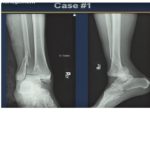

Courtesy: Dr Jordi Sanchez Ballester, FRCS Orth, Liverpool, UK

Key Questions in Ankle Fracture Evaluation

Once a fracture is identified, two critical questions guide management:

Is the fracture displaced or undisplaced?

Is the fracture stable or unstable?

Key Indicator: Talar Shift

Radiographic Criteria

Medial clear space > 4 mm

OR -

Medial clear space > 2 mm more than superior clear space

Presence of talar shift = Displaced & unstable fracture